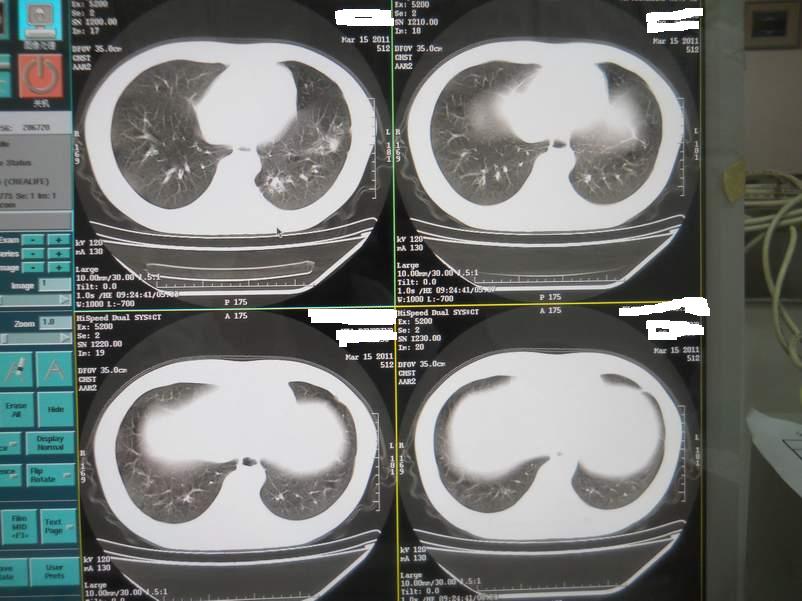

肺霉菌感染

男,22岁,一年前诊断马尔菲尼青霉菌感染,多次复查CT。多次HIV阴性。最近两次CT图片。有实验室结果。

最近实验室检查结果:霉菌感染。